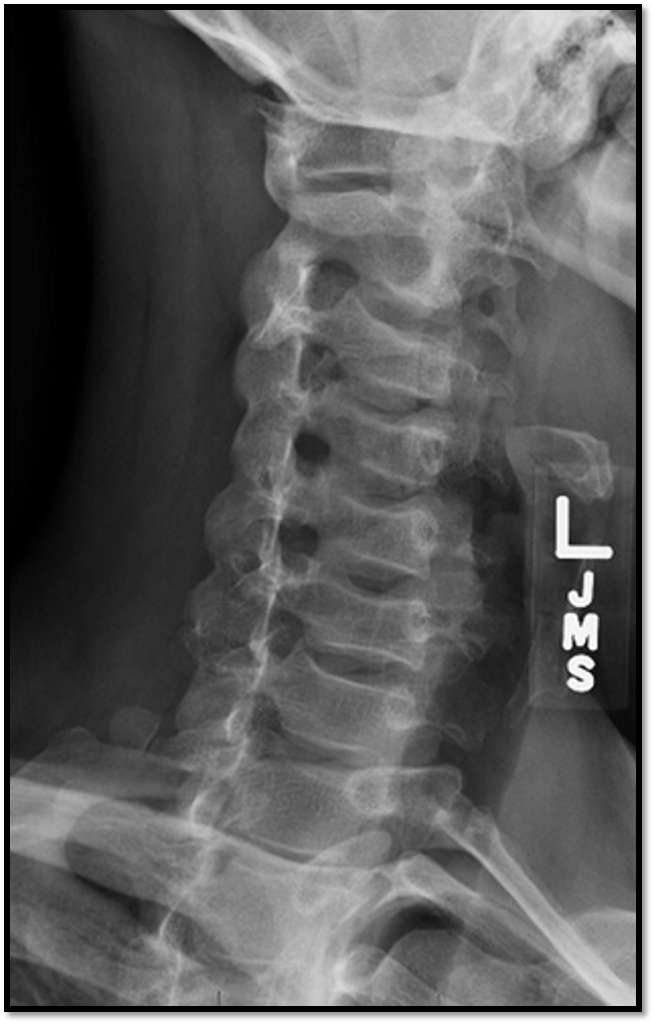

3

Q

A

• rotation and tilt issue

• swimmers not needed (fusion of C6/C7)